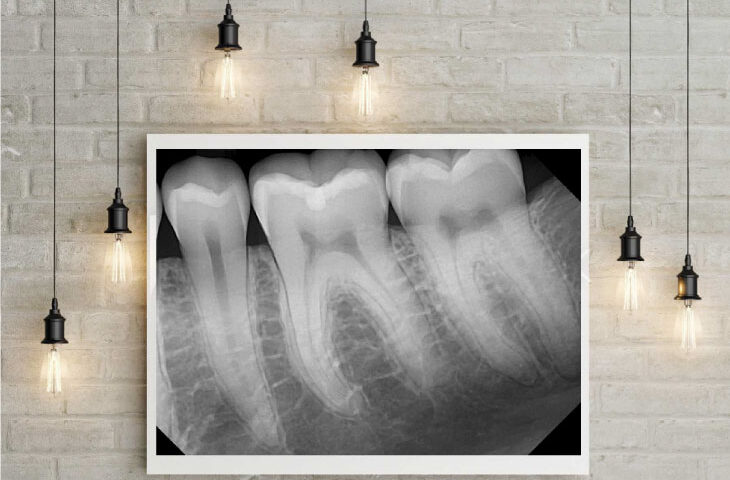

Ramey took an X-ray of Arnett and a few seconds later, Christensen, a renowned prosthodontist, exclaimed, "Nice image!" according to Ramey. The group of experts stood up from their seats and gathered around Christensen, eager to examine the image on his laptop. Ramey recalls this moment with great pride.

"Over time, this secret sauce that he came up with, just the right exposure rates, the right settings, the filters, the software, and just the right combination, he was able to produce these beautiful images," Arnett said.

Just as people used to turn the radio dial to hear the music without any static or noise on analog radios, Ramey said he "dials in" the image that they capture with DentiMax sensors by finding the optimal exposure settings on the X-ray heads to get the best raw image possible. Then he applies the best filters, enhancements, and algorithms to get the perfect image according to each doctor’s preferences.

"No one else does that," Ramey said. "They have different algorithms in their software that try to optimize the energy that hits the sensor and make the best image they can with it. I do it the opposite way. I find the optimal amount of energy first, get the best raw image I can, and then I make it look good," he added.